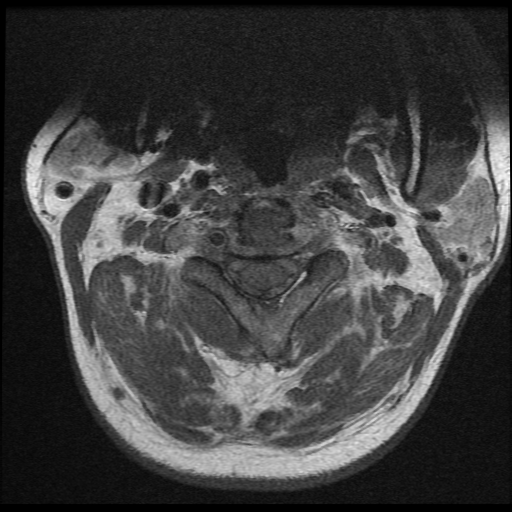

Se observa perdida de la lordosis normal de la columna cervical.

Se observa hipo intensidad del ligamento longitudinal anterior y posterior de la columna cervical, también se observa perdida de la movilidad y rigidez de la misma, los ligamentos interespinosos se ven hipointensos en T2 y en T1, al igual que el pliegue nucal, lo que sugiere calcificación de estas estructuras anatómicas.

Se observa fusión de las vertebras cervicales 5-6 y 6-7, dando la apariencia de bambú.